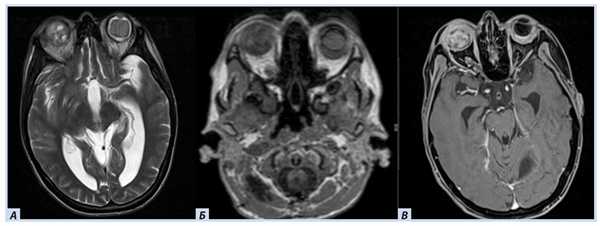

Лучевые методы. На МРТ-изображениях головного мозга выявлено характерное двустороннее поражение глаз (рис. 1), по данным КТ — с участками обызвествления (рис. 2). Также на КТ головного мозга были выявлены зона послеоперационных кистозно-глиозных изменений с наличием кисты и узла на уровне посттрепанационного дефекта в правом полушарии мозжечка, а также аналогичные зоны дорзальнее и в субкортикальных отделах; в левой гемисфере мозжечка определялись кистозные изменения (рис. 3).

Рис. 1. Пациентка П., 30 лет, с диагнозом «Болезнь Гиппеля−Линдау»: магнитно-резонансная томография головного мозга

Примечание. А, Б — Т2- и Т1-взвешенные изображения. В полости правой глазницы объемное образование с неоднородным МР-сигналом; В — постконтрастное Т1-взвешенное изображение, режим подавления сигнала от жира: определяется интенсивное, но гетерогенное контрастирование образования. Кровоизлияние в сетчатку справа.

Рис. 3. Пациентка П., 30 лет, с диагнозом «Болезнь Гиппеля−Линдау»: магнитно-резонансная томография головного мозга

Примечание. А — Tirm-режим: на фоне кист мозжечка визуализируется мягкотканный компонент, прилегающий к кисте справа; Б — DWI-режим: зона рестрикции диффузии по ходу стенки кисты справа; В — постконтрастное Т1-взвешенное изображение, режим подавления сигнала от жира: в той же зоне отмечается накопление.